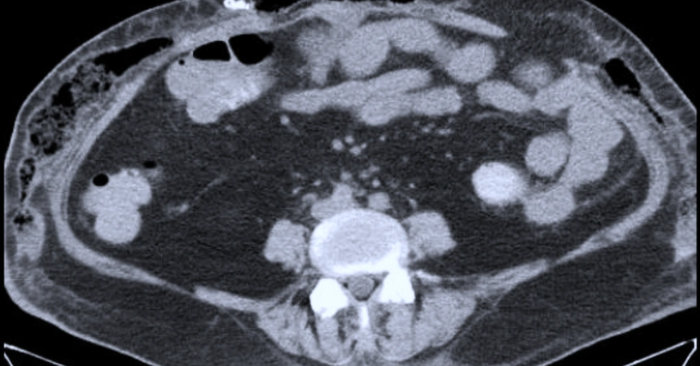

Người phụ nữ có tiền sử đái tháo đường, tăng huyết áp và béo phì đi hút mỡ tại cơ sở tư nhân.trong quá trình phẫu thuật bị rơi vào tình trạng suy hô hấp và sốc nhiễm khuẩn. Bệnh nhân nhập Bệnh viện Quân y 175 trong tình trạng tổn thương đa cơ quan cùng vùng bụng phù nề và đau dữ dội. Kết quả chụp CT cho thấy tràn khí dưới da, tụ dịch và thoát vị thành bụng, làm tăng mức nguy hiểm của biến chứng hút mỡ.